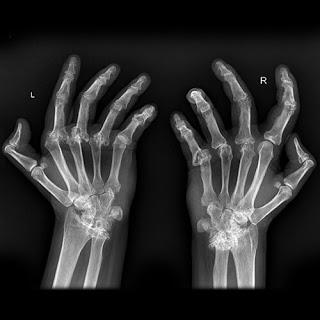

Esta enfermedad reumática puede afectar a la cadera, la zona lumbar y la cervical, pero este mal suele localizarse sobre todo en la rodilla y en la mano. La artrosis impide realizar rutinas cotidianas como caminar o abrir y cerrar la mano. La obesidad y la falta de ejercicio físico propician la aparición de esta enfermedad crónica que se puede combatir con unos hábitos de vida saludables como practicar algún deporte y mantener una dieta equilibrada.

Es más común que lo padezcan las mujeres, y sus síntomas comienzan a notarse desde los 20 hasta los los 50 años de edad. Según la Organización Mundial de la Salud (OMS), las enfermedades reumáticas , como la artrosis, supondrán la principal causa de discapacidad en 2020.La artrosis se produce por el desgaste del cartílago que une los huesos y permite el movimiento de las articulaciones. Una vez que aparece, sus síntomas de quedan para toda la vida. Se puede retrasar el proceso con una serie de hábitos y tomar analgésicos en los momentos de más dolor. También se puede recurrir a la operación de la zona afectada con el implante de una prótesis de silicona en lugar del cartílago desgastado.Esta enfermedad aparece con la edad de manera natural la edad, pero una artrosis patológica o dolorosa es causada por los esfuerzos, el sobrepeso y la genética. Uno de los remedios naturales más eficaces para combatir esta patología es el jengibre. Esta planta medicinal es un antiinflamatorio natural que no solo ayudará a adelgazar, si no que también ayudará a combatir enfermedades respiratorias, diabetes y problemas digestivos.